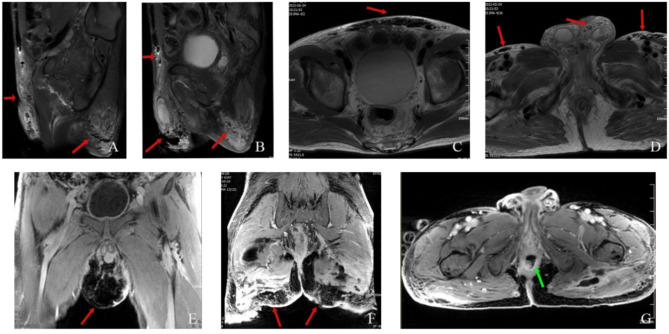

Necrotizing fasciitis (NF) is a rare and life-threatening serious infectious disease, characterized by acute onset and rapid progress, leading to extensive necrosis of skin, soft tissue as well as fascia by a variety of aerobic and anaerobic bacteria, localized on external genitalia, scrotum, groin and perianal areas in males. There exist numerous common etiologies for NF, yet NF induced by malignant neoplasms is exceedingly rare. Several studies have reported that NF may be associated with tumor site (rectal/sigmoid colon cancer) and blood supply dysfunction caused by targeted therapy drugs (bevacizumab, aflibercept, ramucirumab). The perforation of colorectal cancer poses a unique risk factor for NF. However, in our two cases, the patient with rectal cancer received CapeOX (oxaliplatin + capecitabine) + bevacizumab + tislelizumab for 3 cycles without perforation but did develop NF. One month after debridement, the patient continued immunotherapy with tislelizumab alone for the fourth cycle and maintained for an additional 3 cycles without any recurrence of NF. Therefore, does the occurrence of NF correlate with the tumor site (rectum) and targeted immunotherapy? Another patient with hepatocellular carcinoma also developed NF after receiving 2 cycles of lenvatinib + sintilimab treatment. The third cycle of sintilimab immunotherapy was administered on the 13th day after operation, which was subsequently maintained for an additional 2 cycles without recurrence of NF. The absence of a direct correlation between hepatocellular carcinoma and rectal tumor location as well as immunotherapy, suggests that NF may be closely linked to targeted therapy.